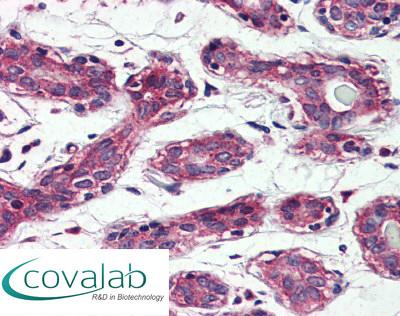

Anti-TAOK1 antibody IHC staining of formalin-fixed, paraffin-embedded human breast after heat-induced antigen retrieval.